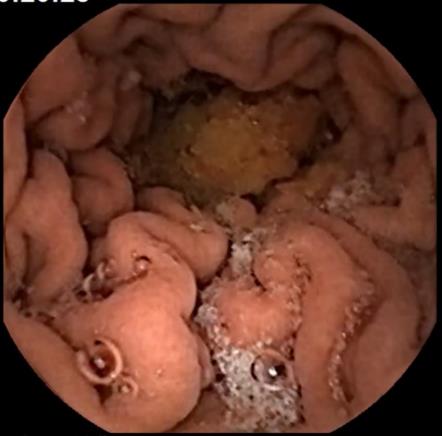

14. Ovako izgleda unutrašnjost vašeg stomaka kada hrana uđe u njega.